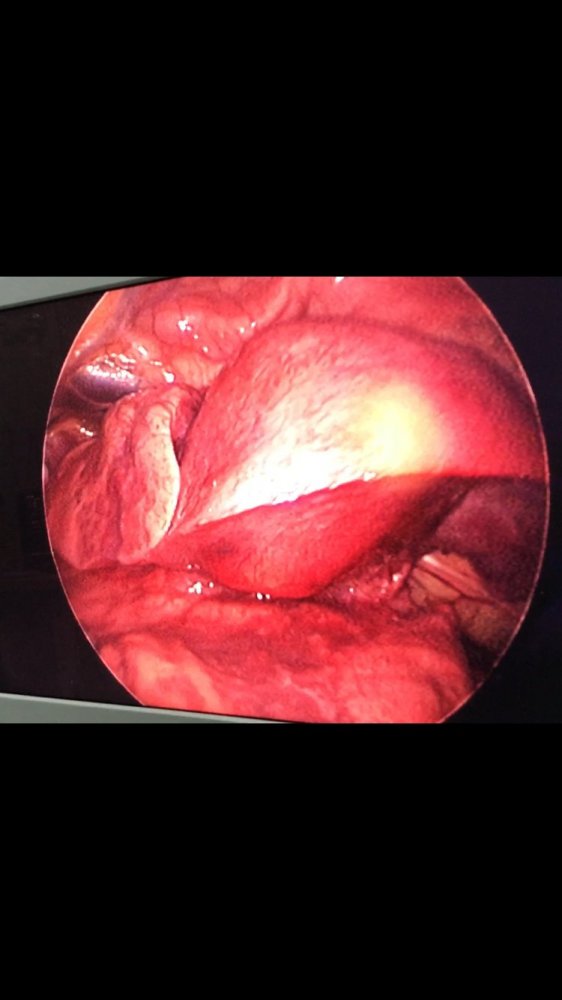

MediastinalTeratoma .Torokoskopik teratomanın eksiziyası

Daha bir çətin əməliyyat 8 yaşlı pasientdə döş boşluğunda törəmə- Ağciyərin orta payı üzərində böyük həcmli törəmə Teratoma. Torokoskopik törəmənin eksiziyası